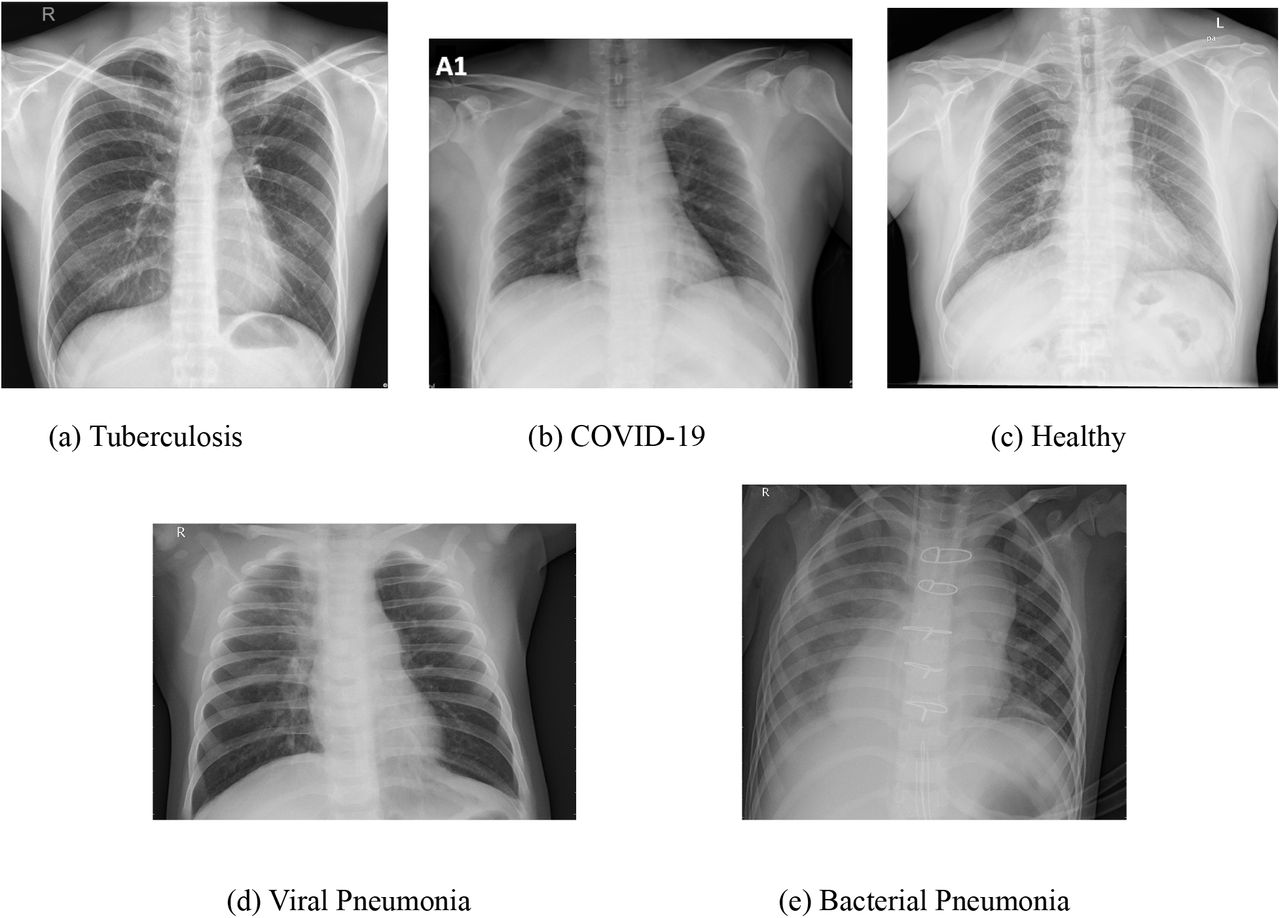

Zapalenie płuc na zdjęciu RTG objawia się przede wszystkim zacienieniami miąższu płucnego, które radiolog ocenia pod kątem rozległości i charakteru. W typowym obrazie bakteryjnego zapalenia płuc, takiego jak pneumokokowe, dominuje konsolidacja – homogeniczne zacienienie obejmujące cały płat płucny, np. dolny prawy (u 40-50% pacjentów wg badań z lat 2018-2022 w European Respiratory Journal). Nacieki zapalne tworzą „pianę” lub mleczne obszary, kontrastujące z przeziernością zdrowego miąższu. Wczesne stadia mogą przypominać mgłę (zacienienia szkliste, ground-glass opacities), szczególnie w wirusowych formach, jak COVID-19, gdzie wykrywalność sięga 60-80% na standardowym RTG klatki piersiowej. Radiolog szuka też poszerzenia naczyniowego lub linii Kerleya, wskazujących na obrzęk śródmiąższowy. Czy zawsze zapalenie płuc daje wyraźne zmiany na zdjęciu RTG? Nie – u 10-20% chorych obraz bywa subtelny, przede wszystkim w odmieńcach u dzieci lub starszych.

- Homogenna konsolidacja płata: klasyka pneumonii bakteryjnej, np. Streptococcus pneumoniae.

- Zacienienia szkliste (GGO): wirusowe etiologie, jak RSV lub SARS-CoV-2 (widoczne u 75% hospitalizowanych).

- Naciek z air bronchogramem: potwierdza zapalenie miąższowe.

- Drobne nacieki guzkowate: atypowe zapalenie, np. Mycoplasma pneumoniae.

- Rozlane zacienienia interstycjalne: wczesna faza lub grzybicze.